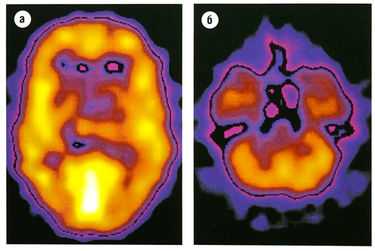

Рис. 8.25 Кортикальное распределение ГАМКд-рецепторных комплексов. Изображение получено с помощью радиоактивно меченного аналога бензодиазепина ломазенила и однофотонной эмиссионной компьютерной томографии. Самые светлые области имеют наивысшую плотность рецепторов, (а) Изображение на уровне среднезатылочной коры, (б) Изображение на уровне мозжечка.

ГАМК — аминокислота, действующая прежде всего на ГАМКд- и ГАМКв-рецепторы. ГАМКА-рецепторы присутствуют на 40% нейронов. Кортикальное распределение ГАМКд изображено на рис. 8.25. С1'-канал зависит от ГАМКА-рецептора, в то время как ГАМКв-рецепторы соединены с G-белками.